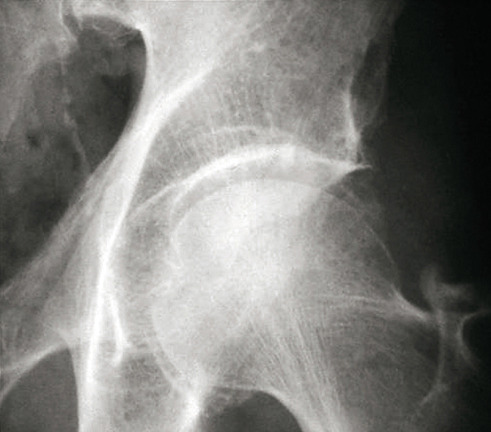

La forme pseudorhumatoïde est rare (5 %), simulant une polyarthrite rhumatoïde. L’arthrite chronique à PPC se présente comme une oligo- ou une polyarthrite, avec parfois des signes systémiques d’inflammation (élévation de la vitesse de sédimentation et de la protéine C-réactive [CRP]). La superposition d’accès aigus microcristallins est évocatrice de ce diagnostic. Il s’agit d’un diagnostic différentiel de polyarthrite rhumatoïde du sujet âgé ou de pseudopolyarthrite rhizomélique. Le diagnostic repose sur la mise en évidence des cristaux de PPC, même si les radiographies standard sont évocatrices. L’atteinte radiographique associe des calcifications des cartilages articulaires (fig. 7) et des fibrocartilages (fig. 8, 9, 10 et 11) [à rechercher systématiquement sur les radiographies de poignets, genoux et symphyse pubienne]. La mise en évidence d’une chondrocalcinose sur des radiographies standard renforce le diagnostic de rhumatisme à PPC mais l’absence de dépôts calciques ne l’élimine pas (la sensibilité de la radiographie standard étant imparfaite). L’échographie peut mettre en évidence des dépôts de PPC, qui apparaissent comme une fine bande hyperéchogène au sein des cartilages hyalins et comme des points scintillants dans les fibrocartilages ou dans la membrane synoviale. La sensibilité de l’échographie est bien supérieure à celle de la radiographie standard. Le scanner peut également mettre en évidence des dépôts calciques évocateurs, notamment au niveau du rachis ou du bassin qui sont plus difficilement explorés par les radiographies et l’échographie.

Les arthropathies liées à l’arthrose ou destructrices ont une fréquence qui augmente avec l’âge. L’arthrose associée aux dépôts de PPC touche en particulier les genoux, avec une symptomatologie chronique et/ou des accès aigus cristallins. Par comparaison avec l’arthrose idiopathique, l’arthrose avec dépôt de PPC serait à l’origine d’une symptomatologie plus inflammatoire, toucherait des articulations inhabituelles (radiocarpienne, carpienne, gléno-humérale, médio-pied et arrière-pied, cheville) et serait associée à plus d’ostéophytes et de géodes. Cette arthropathie dégénérative peut s’accompagner de lésions structurales sévères avec disparition rapide de l’interligne (arthropathies destructrices : hanches, genoux, poignets, coudes) mimant une ostéo­arthropathie nerveuse.